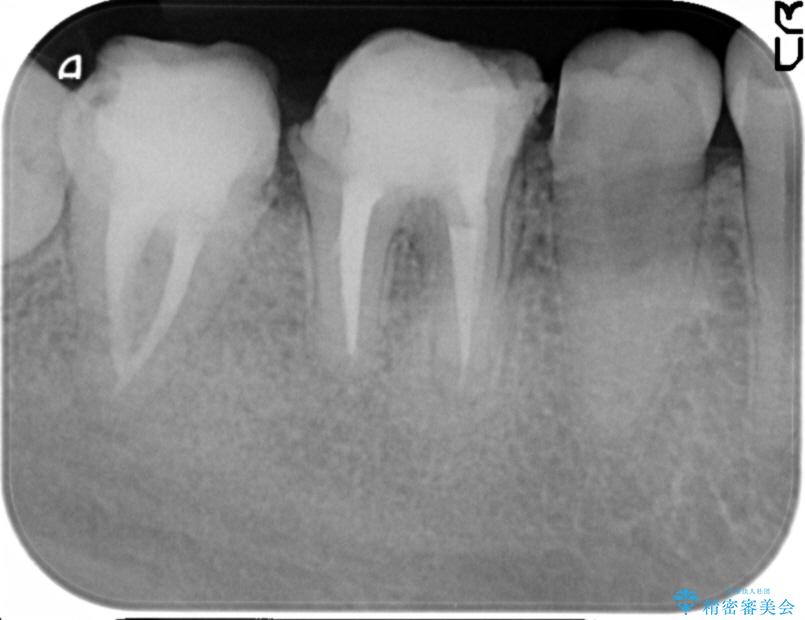

奥歯は既に根管治療が為されクラウンを装着する必要性がある状態ですが、歯の高さが低くクラウンの安定性・強度を担保するために歯周外科を行う治療計画としました。

歯周外科を行うことで、歯ぐきの位置を下げ歯の高さを作り出し安定したクラウンの装着が可能となります。また同時に舌の邪魔となっていた骨隆起の除去を行うこととしました。